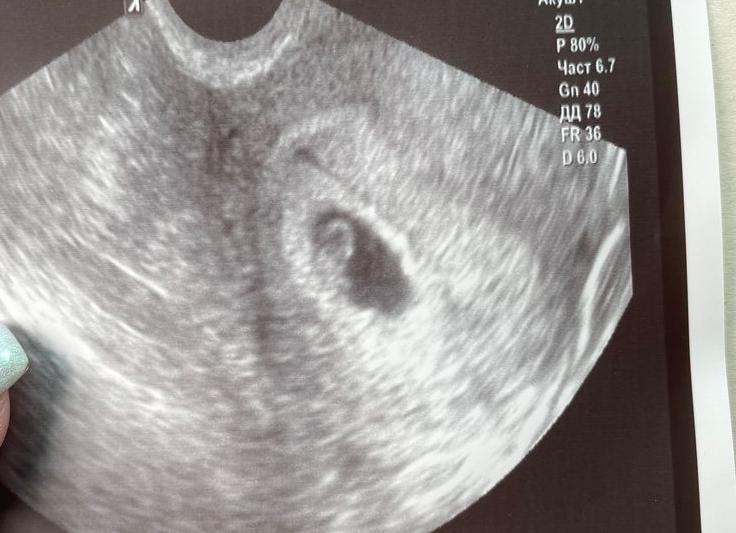

Абдоминальное УЗИ (от abdominous — живот, брюхо) — это метод ультразвуковой диагностики органов брюшной полости и малого таза, проводимый через брюшную стенку при помощи специального датчика с трансдьюсером внутри (transducer). Прибор распознаёт импульс, отражающийся от органа, и преобразует его в электрический сигнал.